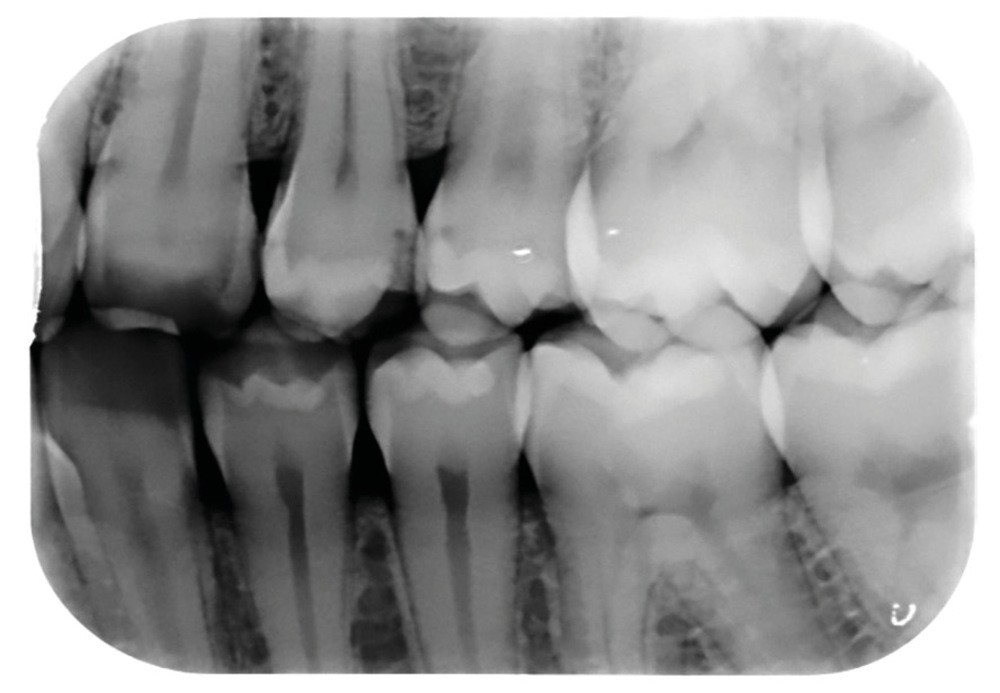

FAUX. Le diagnostic précoce des lésions carieuses se base sur un diagnostic clinique visuel précis à l’aide des classifications visuelles internationales (ICDAS ou ICCMS) et de l’utilisation d’aides optiques (loupes, microscope, caméra avec signal fluorescent ou non) et sur un diagnostic radiographique (à l’aide de deux bitewing, l’un à droite l’autre à gauche) (fig. 1).